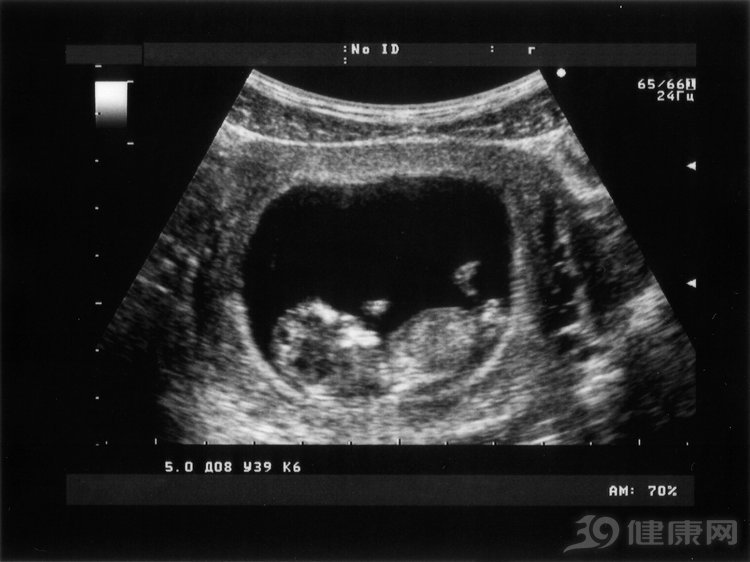

上面的切身经历,看着有点可怕,但仔细琢磨,多是她自己的心理作用。其实,阴式B超的确没有想象的可怕,而且常用于妇产科的产检、子宫检查,还有子宫附件检查等,是一种腔内超声。

方法是接受检查的女士在排空尿液后,用特定的B超检查设备(上面说的“长长的棍子”)放入女性阴道里,检查子宫卵巢等位置。

通过阴式B超检查的疾病范围非常广,比如可以排卵是否正常、子宫和卵巢是否有良性或恶性肿瘤、卵巢囊肿、巧克力囊肿等。此外,阴式B超对确诊宫外孕、早期妊娠都有重要作用。